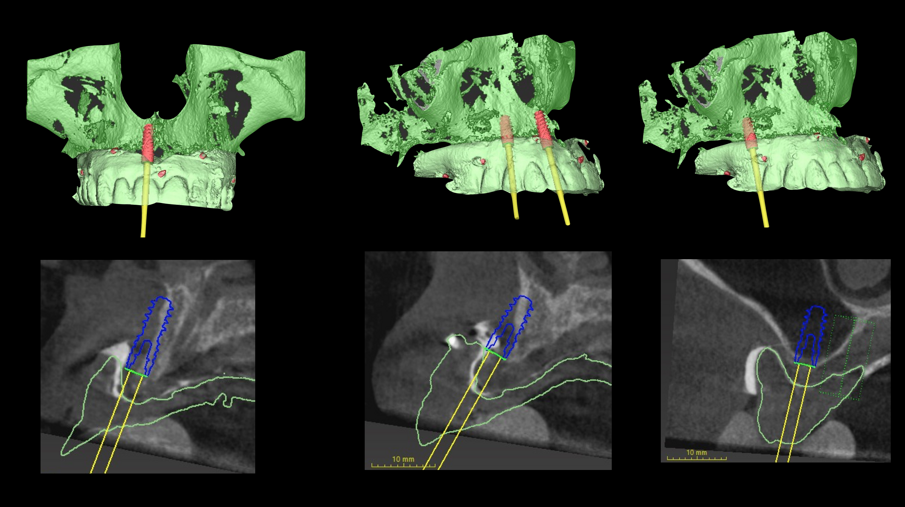

Inoltre da questa nuova ceratura dobbiamo ricavare una protesi radiografica con i punti di repere radiopachi che ci servirà per fare il matching con i nuovi file DICOM dell’osso rigenerato (Figg. 35, 36). Fatte le opportune verifiche nel software di chirurgia guidata, si pianifica l’intervento di posizionamento implantare (Figg. 37-40). Si programma lo stesso giorno della chirurgia anche il carico immediato degli impianti; decisione supportata dalla verifica istologica dell’osso rigenerato che dovrà comunque essere confermata il giorno del posizionamento implantare durante il quale si misurerà il torque di inserimento degli impianti e la stabilità primaria con il sistema OSSTELL mentor (Integration Diagnostics) che sfrutta l’analisi della frequenza di risonanza.

Grazie al flusso digitale, possiamo inserie nel software anche il file STL del provvisorio pre-chirurgico preparato e quindi progettare il provvisorio immediato (Fig. 41). La pianificazione degli impianti a questo punto viene effettuata in modo protesicamente guidato ed è facile posizionare correttamente l’impianto e verificarlo nelle cross del software. Si progetta e si disegna quindi la dima chirurgica (Fig. 42). Il giorno dell’intervento abbiamo già tutto pronto e la paziente presenta uno stato di salute dei tessuti ottimale grazie anche al fatto che ha potuto portare per tutto il periodo una protesi fissa.

Procediamo quindi all’inserimento di sei impianti BLX Straumann (Straumann Group) (Fig. 43, 44), ed utilizziamo gli impianti posizionati nella tuberosità per stabilizzare la dima chirurgica e il provvisorio sul modello master di lavoro digitale. La funzionalizzazione del provvisorio immediato subito dopo l’intervento viene effettuata con l’utilizzo della tecnica DIL19 (Figg. 45, 46).